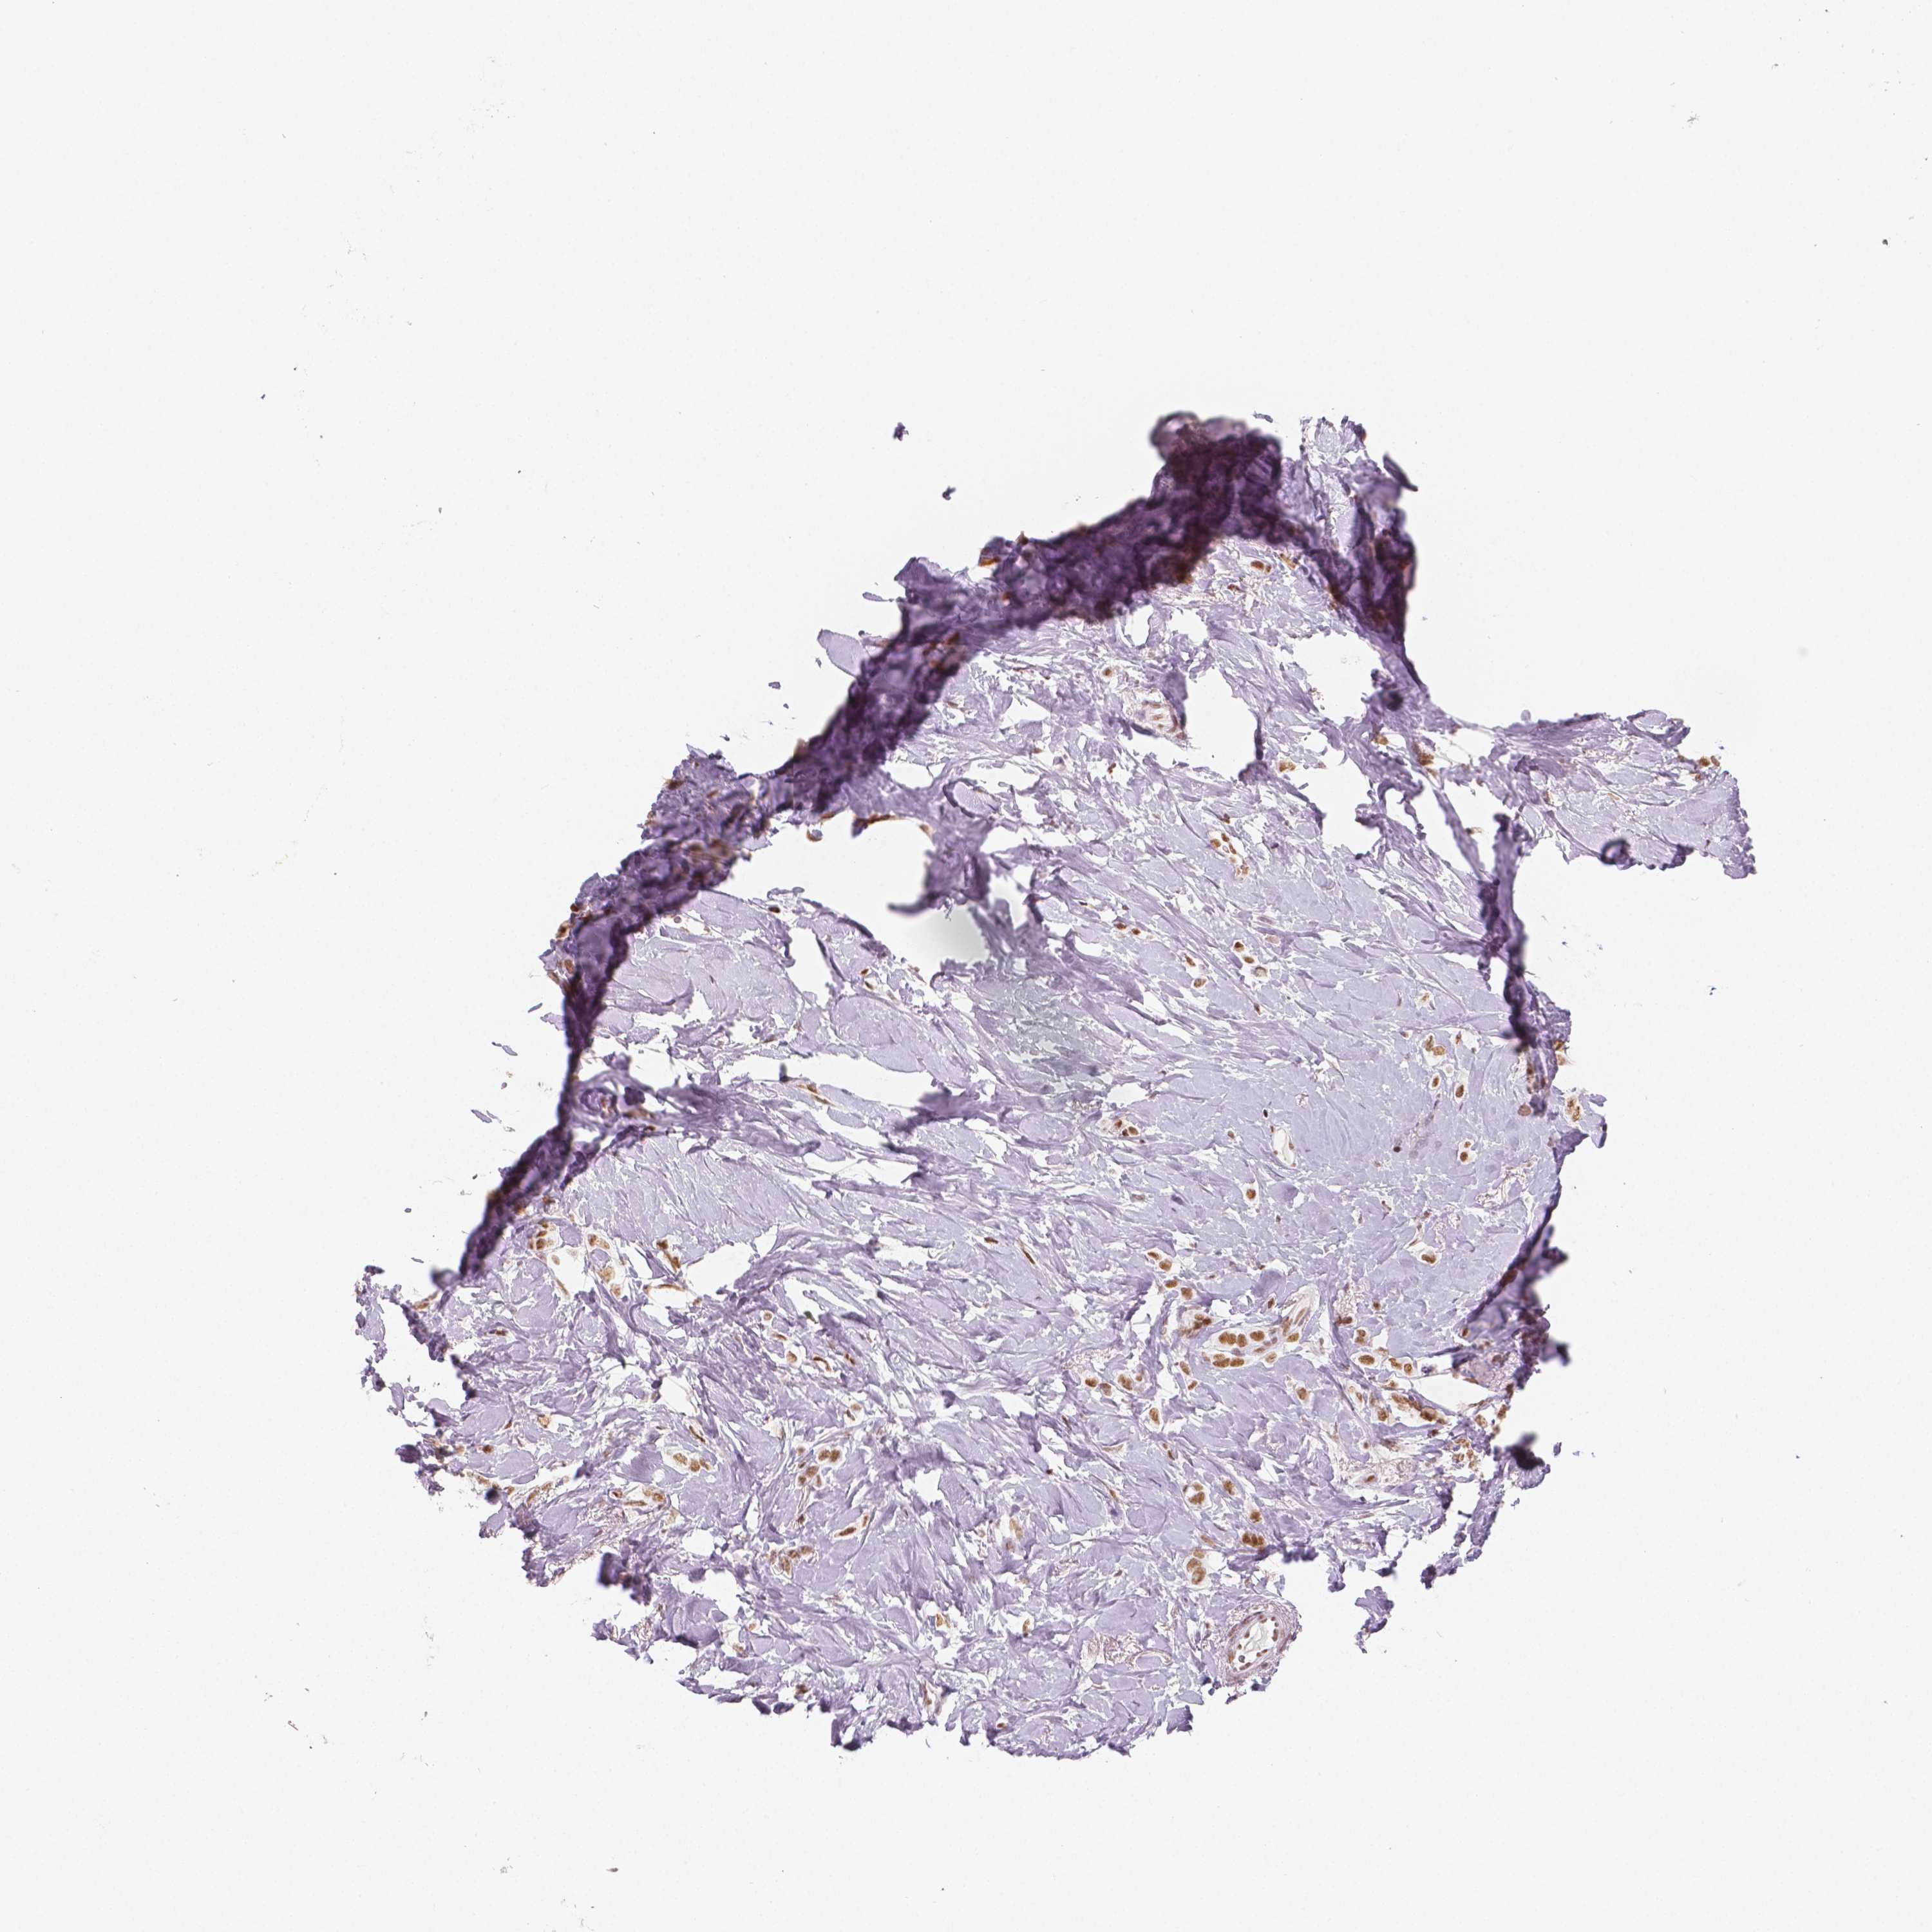

BRCA TCGA BRCA VALIDATION PROTEIN EXPRESSION

ANTIBODIES

AND

VALIDATION